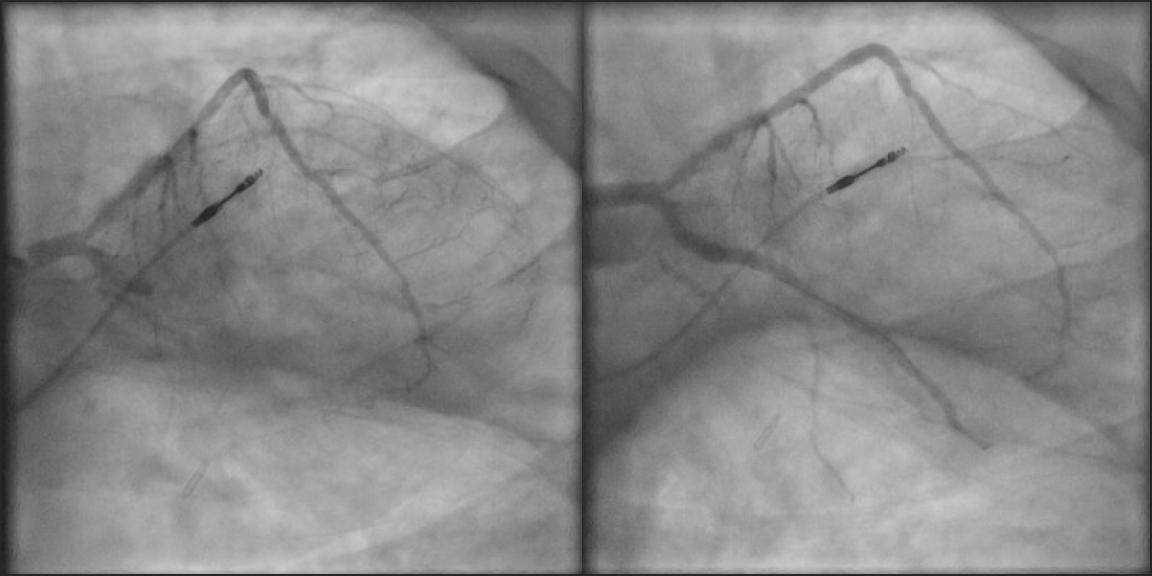

A 58-year-old male with history of primary hypogonadism on testosterone replacement therapy, coronary artery disease with prior myocardial infarction, type 2 diabetes, hypertension, hyperlipidemia, obesity, and obstructive sleep apnea on home CPAP presented with typical anginal chest pain. EKG was consistent with inferior STEMI. He was taken for emergent coronary angiography, revealing the culprit lesion: 100% occlusion of the left circumflex coronary artery (LCx) with TIMI 1 flow. Percutaneous Coronary Intervention (PCI) was performed with placement of two drug-eluting stents, and he was given loading doses of dual antiplatelet therapy. There was significant thrombus present requiring manual aspiration thrombectomy, with intravascular ultrasound confirming underlying atherosclerosis. Ultimately, TIMI 3 flow was achieved. Post-PCI, the patient had significant anginal chest pain refractory to medical management. EKG demonstrated resolution of ST elevations, and echocardiogram showed moderately reduced ejection fraction without pericardial effusion or structural complications. His initial hemoglobin was 23.1 (hematocrit 65%), and testosterone levels were markedly elevated above 1,500.

We suspected coronary thrombosis may have been partially driven by hyper viscosity from polycythemia, so we performed three therapeutic phlebotomy treatments of 500mL each and gave three one-liter intravenous fluid boluses, until hemoglobin levels were below 18. His chest pain improved markedly after phlebotomy, and he was discharged with close cardiology and endocrinology follow-up. JAK2 mutation test was negative, and testosterone supplementation was discontinued for the interim.